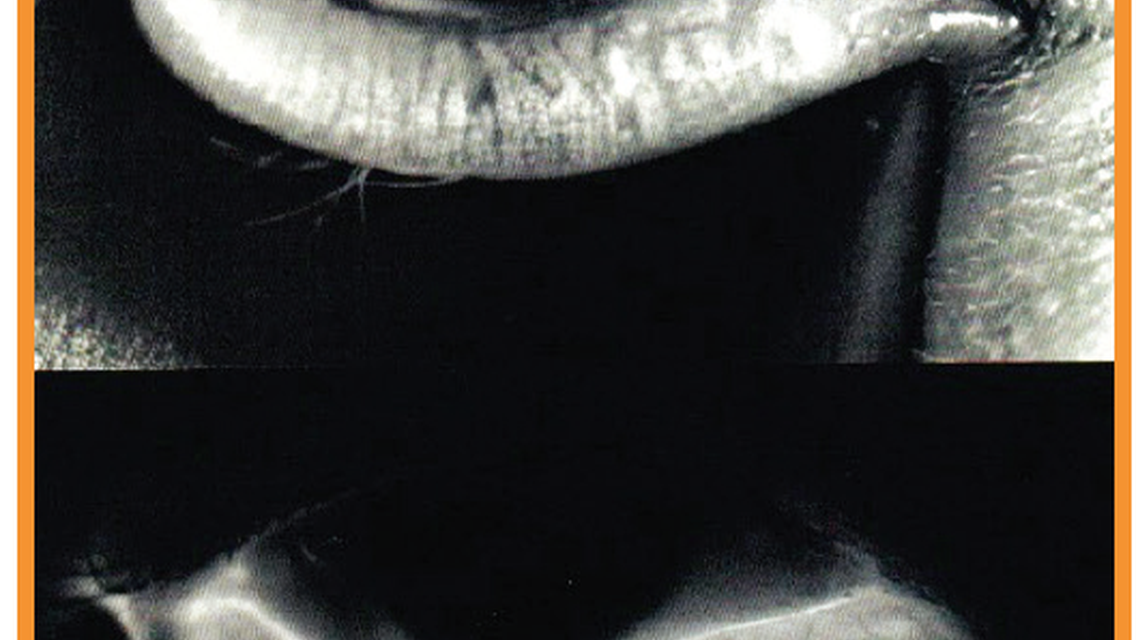

On anterior-segment optical coherence tomography before CXL, the stromal tissue was relatively smooth and structurally organized in both eyes. Two months after CXL, changes in stromal reflectivity can be observed as the tissue is remodeling; a demarcation line is also apparent, which may indicate depth of the CXL effect (Figure 2).3